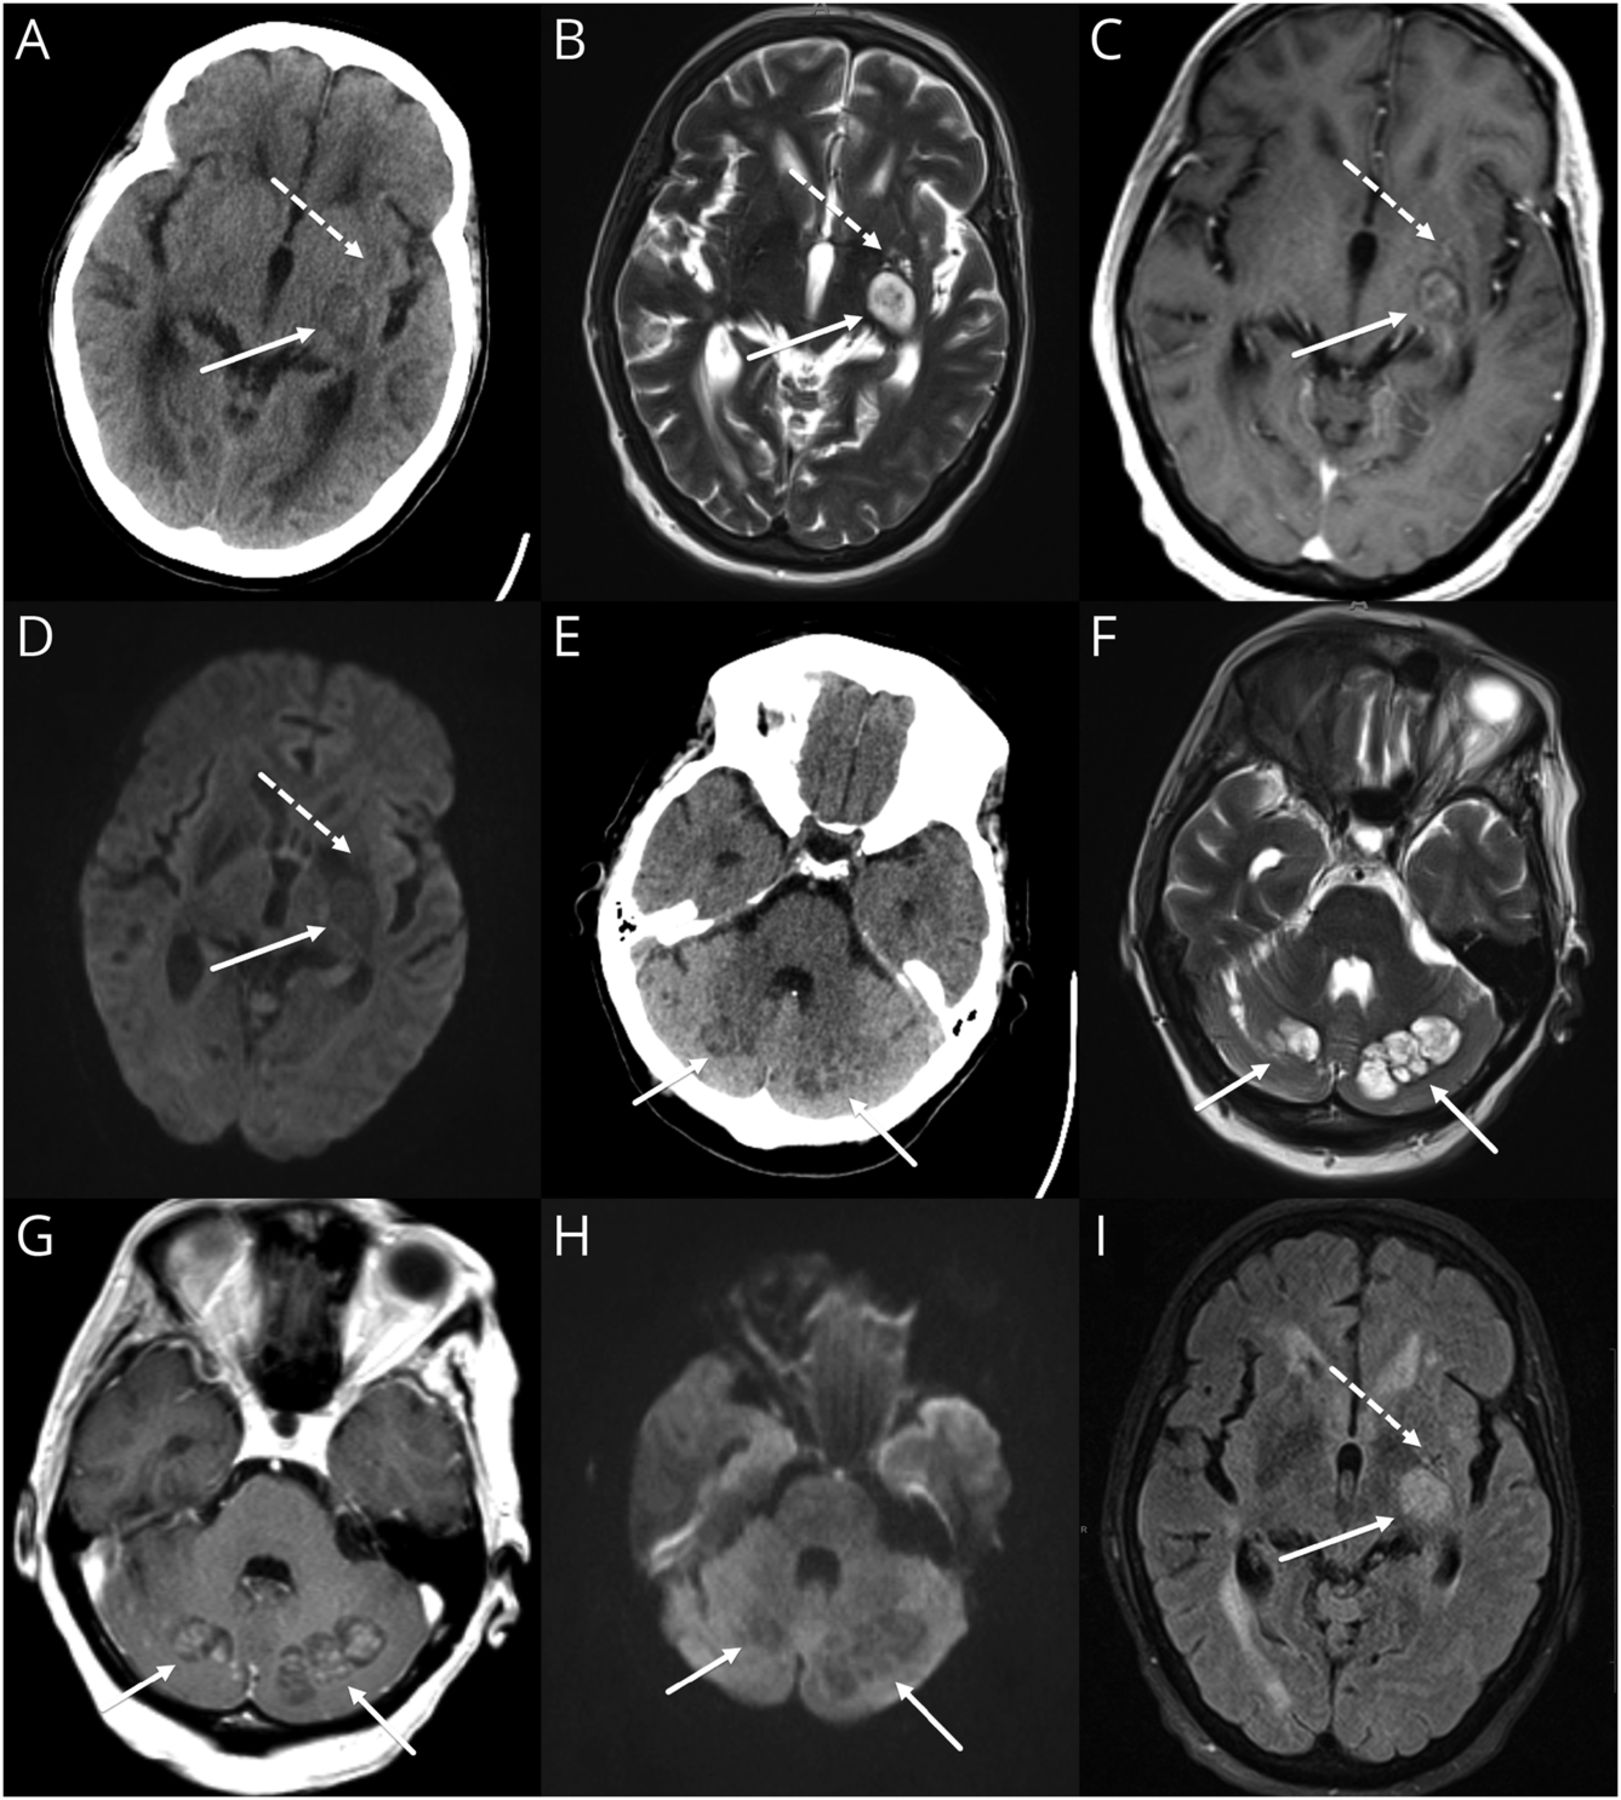

41 CT (E)、MRI T2 (B和F), postcontrast T1 (C和G),醉酒驾车(D和H), T2天赋(I)大脑的图像。切除(实心箭头)合并感染、出现异构hypodense病变在CT。在MRI上,分“脏”T2是典型的外观与内部增强。相比一个典型的脓肿,没有内部限制扩散。假性囊肿在CT(虚线箭头)是糟糕,出现hypodensity的模糊区域。MRI上表现为新扩张血管周的空间。片状增强postcontrast图像和周围水肿才能区别于正常血管周的空间如果成像之前不可用。醉酒驾车= diffusion-weighted成像;天赋= fluid-attenuated反转恢复。

虽然隐球菌病一直被视为一种疾病的免疫力低下,很少免疫活性的个人可以影响(特别是隐球菌gattii)。成像,3表现可能是:(1)脑膜疾病显示脑膜增强,(2)脑膜疾病扩展到血管周的空间,导致膨胀和囊性区(假性囊肿形成),和(3)感染性材料的聚结到弗兰克实质集合(切除)。金宝搏188手机app1